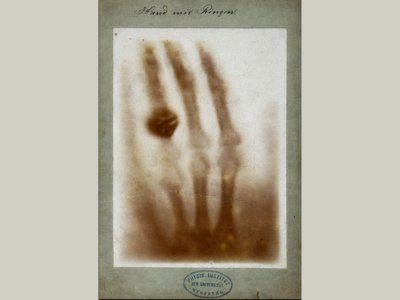

No 22 | Hand mit Ringen (Main avec bague)